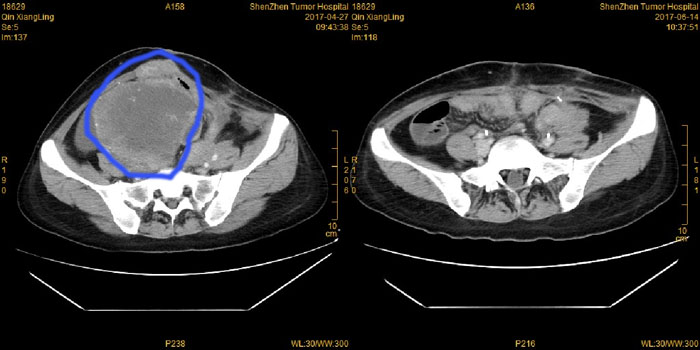

经过我院多学科的讨论以及周密的术前准备之后,2017年5月,李阿姨再次做了手术,切除了一个大小约19cm×15cm ×13cm的巨大腹腔肿物。

手术前、后CT对照